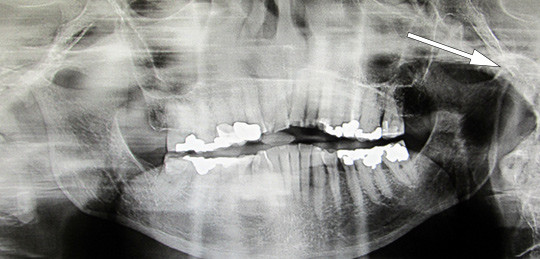

I figur 3 og 4 ser vi et CT-bilde av kjeveleddene og ortopantomogram (OPG) av mandibula hos vår pasient, som viser nærmest fullstendig destruksjon av kondylene på begge sider, noe som forklarer den betydelige retrusjonen av mandibula og bittåpning i fronten på hele fem millimeter. Både det kliniske og det røntgenologiske bildet er forskjellig fra det man vanligvis finner ved kjeveleddsartrose, en lidelse som stort sett er begrenset til leddbrusken og det periartikulære beinet. I dette tilfellet er hele kondylen destruert.